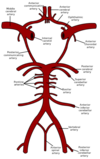

Describe the Blood Brain Barrier

Limits diffusion of substances from the blood to the brain extracellular fluid

Maintains the correct environment for neurones

Brain capillaries have

- Tight junctions between endothelial cells. These tight junctions (bound by clodin and occludin proteins) prevent hydrophilic molecules entering through the capillaries.

- Basement membrane surrounding capillaries

- End feet of astrocyte processes. Astrocytes do not form the barrier but they send chemical messages that tell the endothelial capillaries to form tight junctions.

Due to the tight junctions that exist with the capillaries, specialised transporters need to be put in place to allow the movement of needed molecules across the BBB (this appears to be controlled by signals released from the astrocytes). Substances such as glucose, amino acids, and potassium are transported transcellularly across the BBB, allowing their concentrations to be controlled. Gaseous molecules and H2O can diffuse freely across the BBB, as will any lipophilic molecules